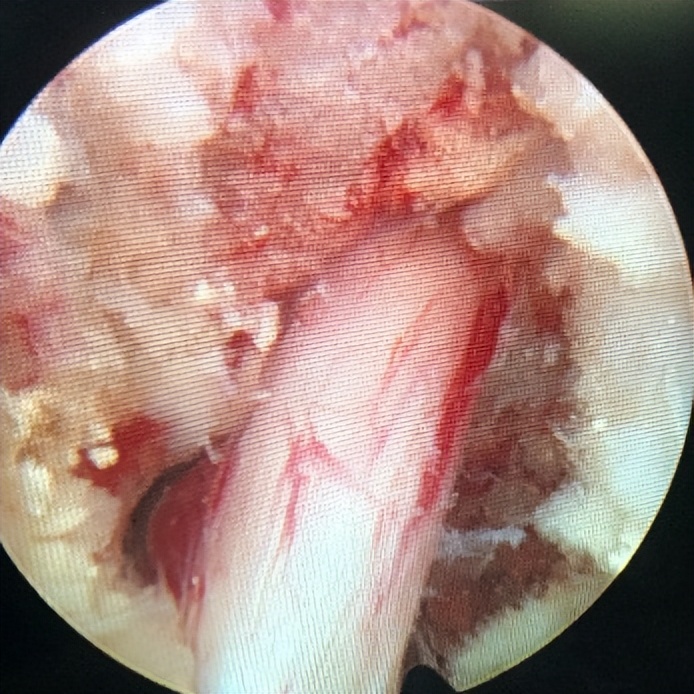

微创椎间孔镜手术 是局部麻醉下,使用放大的内窥镜,对压迫神经的椎间盘组织进行摘除,来缓解患者坐骨神经痛的先进的微创治疗方法。 常见疾病 有腰椎间盘突出症、腰椎管狭窄症、神经根型颈椎病等,其中腰椎间盘突出症尤为常见,同样适用于高龄不能耐受大手术的,多节段狭窄的患者, 此手术风险要明显低于开放手术。